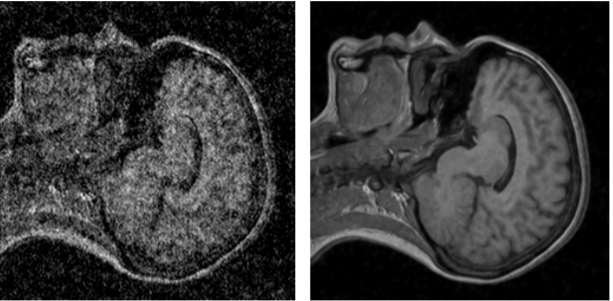

Помимо применения техники в фотографии, в частности в астрофотографии или съемке в темноте, разработчики также предложили применять ее для повышения качества снимков МРТ и продемонстрировали примеры работы алгоритма на таких снимках:

Фото: arxiv.org